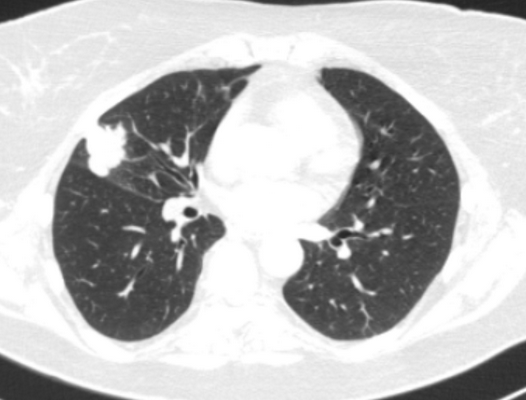

Сканы КТ отличаются более высокой четкостью изображений и информативностью. В ходе компьютерной томографии рентгеновская трубка вместе с чувствительными датчиками совершает несколько оборотов по спиральной траектории, сканируя исследуемую область. Аппарат КТ делает множество сканов толщиной до 1 мм, на основании которых воссоздается трехмерная модель легких, сосудов, органов и костей грудной клетки в высоком разрешении. Таким образом после компьютерной обработки изображений ткани и органы можно исследовать в трех проекциях, эффект наложения теней от органов в случае с компьютерной томографией отсутствует.

Однако большинство медиков склоняются к мнению, что если есть возможность сделать КТ легких вместо рентгена, то лучше исследовать органы грудной клетки именно так. Во-первых, врач точно не пропустит заболевание или опухоль в начальной стадии. Во-вторых, после КТ легких уже нет необходимости в дополнительном уточняющем обследовании (кроме лабораторной диагностики, поскольку инфекционные, вирусные и бактериальные агенты-возбудители определяют с помощью анализа биологического материала). В-третьих, небольшие кальцификаты, деструкции и опухоли видны только на сканах КТ.

Назначить КТ или рентген легких при пневмонии сможет только врач после изучения симптомов, лабораторных анализов, индивидуальной клинической картины пациента. Наличие жидкости или гноя в альвеолах, а также фиброз визуализируется и на рентгенограмме и на сканах КТ. Однако традиционного рентгена при пневмонии I-II степени может быть недостаточно, в то время как на КТ она видна более определенно как «матовые стекла». При атипичной пневмонии и при коронавирусе рекомендуется сделать КТ легких.